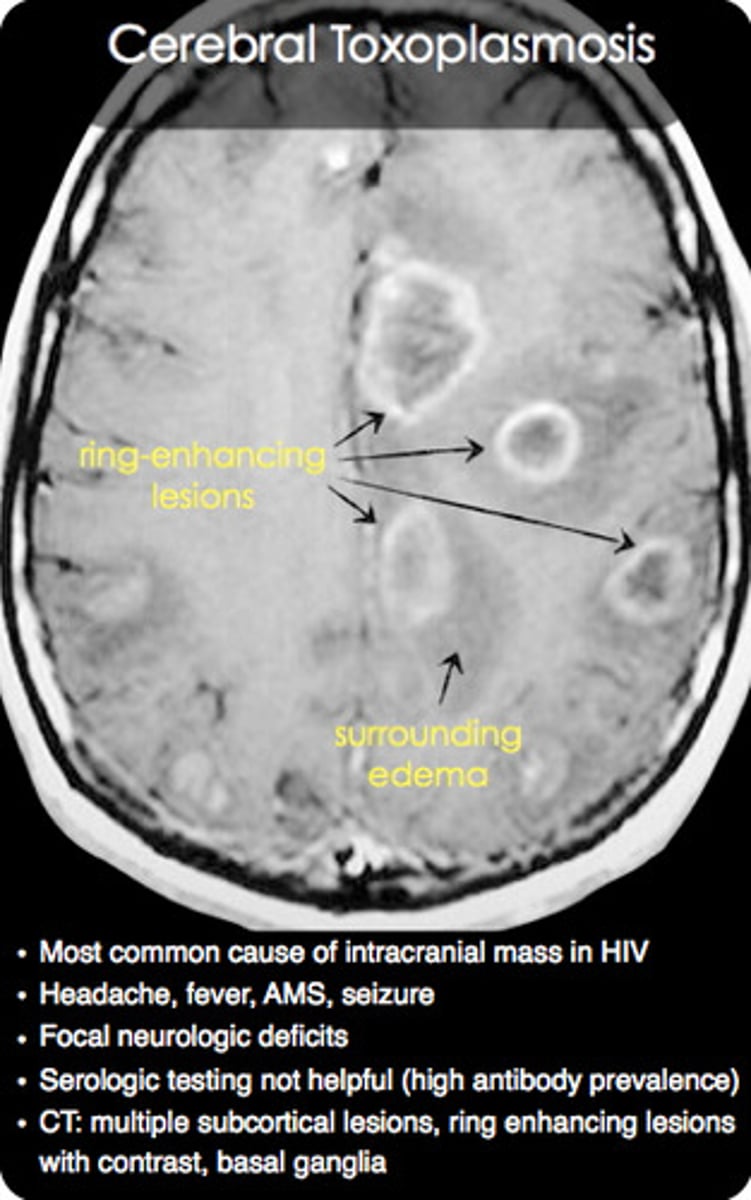

Can you use antibiotics (ex: chloramphenicol or tetracycline) to treat patients with malaria or toxoplasmosis?